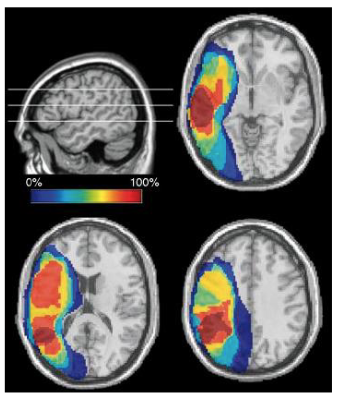

* tDCS

tDCS

Transcranial direct current stimulation

Non-invasive brain stimulation technique that uses low-level electrical currents to modulate brain activity

Treatment time frame: ~10–23hrs over ~28-32 days

Results suggests promoted recovery from aphasia

What’s the difference between tDCS & TMS?

▪ tDCS – constant, weak electrical current and is a neuromodulator

▪ TMS – repeated electromagnetic pulses and is a neuro-stimulator

How do we treat aphasia?

Long repetitive sessions of stimulating the brain is thought to use one of two mechanisms

1. Enhance activity in the areas immediately surrounding the lesion

2. Enhance activity on the contralateral side, creating a compensatory effect

The mechanisms rely on neuroplasticity

Neuroplasticity: the brain’s ability to change and adapt structure & function